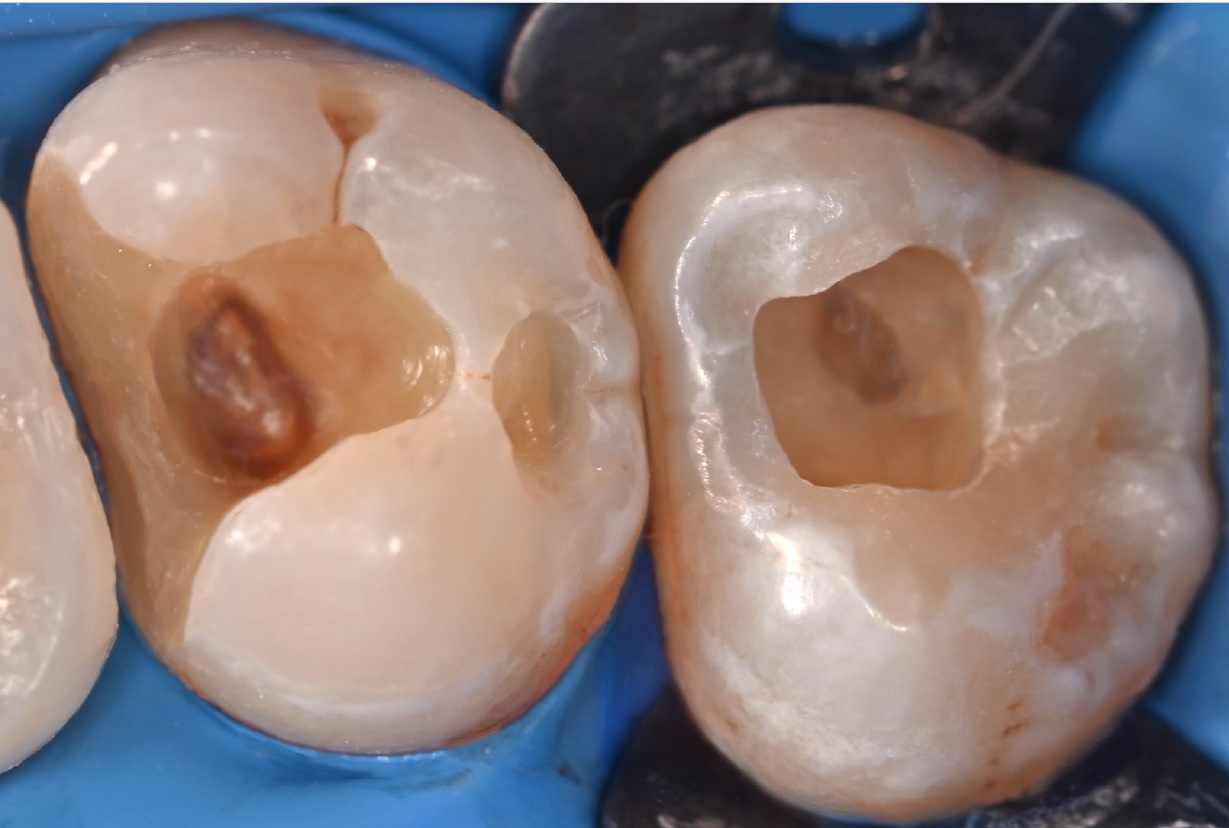

Εικ. 2: Η σωστή εφαρμογή του ελαστικού απομονωτήρα και η εξακρίβωση της πλήρους απομόνωσης είναι απαραίτητες πριν από τη διάνοιξη της κοιλότητας για την αποφυγή περαιτέρω μόλυνσης, ιδιαίτερα σε περιπτώσεις άμεσης ή έμμεσης επικάλυψης του πολφού.

Εικ. 3: Μετά την αφαίρεση της προηγούμενης αποκατάστασης σύνθετης ρητίνης και τον καθαρισμό της τερηδονισμένης αλλοίωσης στον τρίτο γομφίο, παρατηρήθηκε μια βαθιά κοιλότητα κοντά στον πολφό. Και στις δύο περιπτώσεις, αποφασίστηκε η εφαρμογή του Biodentine XP χρησιμοποιώντας μια τεχνική biobulk-fill για την έμμεση κάλυψη του πολφού, με σκοπό την αποκατάστασης της οδοντίνης, την παροχή ενός προστατευτικού φραγμού και τη διατήρηση της ζωτικότητας του δοντιού.